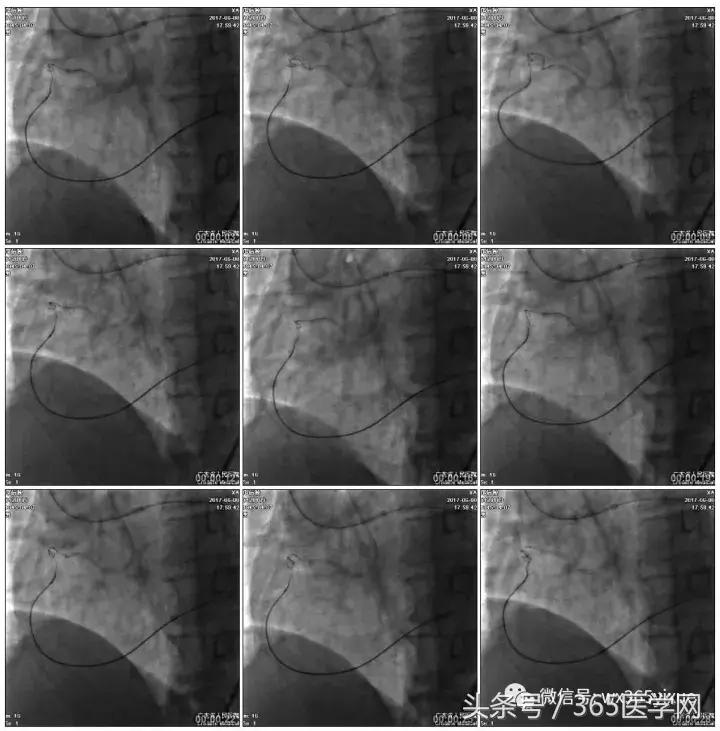

第三步:1月后

介入策略

正向浅尝,改为逆向,LCX-PL

RRA:6F AL0.75 GC –RCA;

RFA:7F XB 3.5 GC—LCA 150cmcorsair

正向130cmFinecross微导管支持下尝试送PILOT150、Gaia 2导丝无法通过RCA闭塞段

SION导丝通过侧枝

逆向导丝:更换Gaia2

正向导丝:Gaia2,PILT150

正向导丝knuckle

2.5*15mm球囊扩张,逆向导丝尝试,但未能进入正向GC

1.正向2.5*15mm球囊扩张,Reverse CART

2.Guidezilla延长导管辅助下,逆向导丝进入正向GC